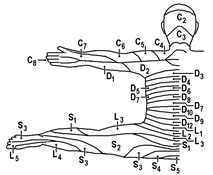

Ноцицептивная стимуляция внутреннего органа часто вызывает ощущение боли не в нем самом, а в отдаленных, поверхностных частях тела, или не только в нем самом, а также в отдаленных частях тела. Такая боль называется отраженной. Как правило, она охватывает участки периферии, иннервируемые тем же сегментом спинного мозга, что и затронутый внутренний орган. Иными словами, на поверхности кожи боль проявляется в соответствующем дерматоме (рис.).

Вспомним! Дерматом – ограниченная область кожи, которую иннервирует афференты одного заднего корешка. В скелетной мускулатуре эквивалентами дерматомов являются миотомы.

Рис.. Дерматомы. Вид сзади.